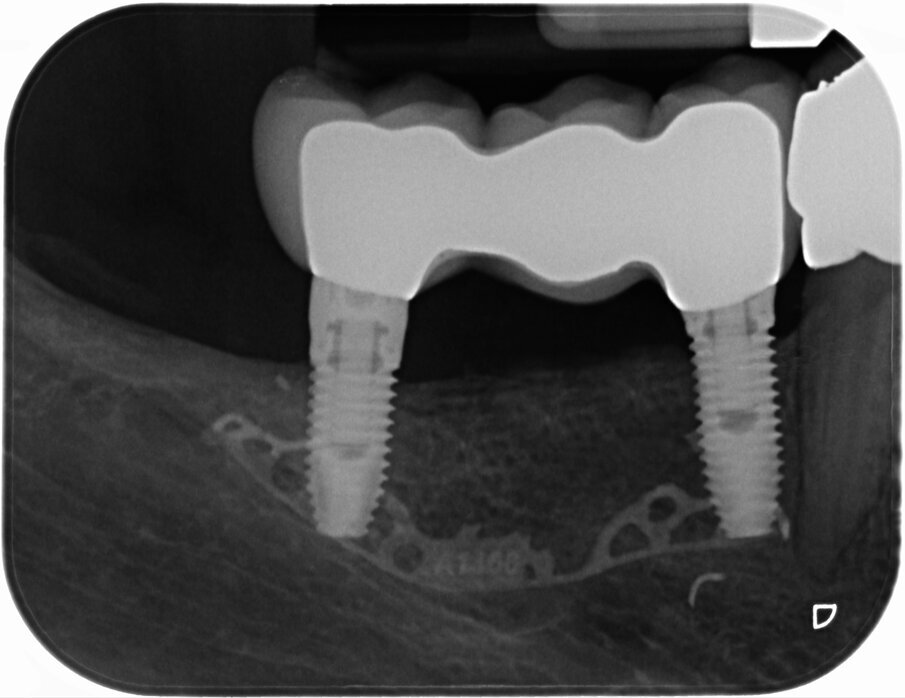

La paziente è stata dimessa con la seguente terapia domiciliare: una dieta fredda e liquida per le prime 24 ore e una dieta tiepida e morbida fino alla rimozione dei punti di sutura, oltre alla continuazione della terapia antibiotica, antisettica e antiedemigena associata alla terapia antidolorifica con ketoprofene e sale di lisina, bustina da 80 mg, al bisogno. Subito dopo l’intervento è stata eseguita una CBCT di controllo per verificare l’incremento ottenuto (Figg. 6a, 6b). Le suture sono state rimosse 20 giorni dopo l’intervento e la paziente è stata sottoposta a controlli clinici a 1-3-6 mesi dall’intervento che non hanno evidenziato alcuna complicanza. Al sesto mese, è stata eseguita una nuova CBCT (Fig. 7), utilizzando la medesima dima diagnostica usata in fase pre-operatoria, che ha mostrato la corretta integrazione del materiale innestato (Fig. 8) e, a 7 mesi dall’intervento, si è proceduto alla rimozione della griglia e all’inserimento di due impianti “root form” e “bone level” nella zona rigenerata. Un lembo in cresta a tutto spessore, simile a quello eseguito nella prima fase chirurgica, ha permesso l’accesso alla griglia e la stessa dima utilizzata per la diagnosi è stata adattata creando fori di circa 4 mm di diametro per ottimizzare il posizionamento degli impianti (Fig. 9).

I due impianti (4 x 10 in sede 4.4 e 4 x 8.5 in sede 46 – Nobel Biocare AG – Kloten, Switzerland) sono stati inseriti con modalità sommersa e con un torque di 45 Ncm. Al momento della rimozione della griglia (Fig. 10) non è stata visibile alcuna significativa perdita ossea e il tessuto osseo rigenerato è apparso di notevole consistenza, tanto che alcuni frammenti della periferia della griglia, completamente ricoperti da osso neoformato, sono stati lasciati in situ per evitare rimozione di tessuto osso e perché non interferivano con l’inserimento implantare. L’analisi istomorfometrica del prelievo osseo eseguito con una fresa iniziale cava di 2.5 mm nel futuro sito implantare in posizione 4.4, ha mostrato la presenza di una matrice vitale e densa e senza focolai infiammatori. Durante la fase di riapertura degli impianti, eseguita a gennaio 2019, a causa di una inadeguata banda di mucosa cheratinizzata sul versante vestibolare, è stato eseguito un intervento di vestiboloplastica mediante affondamento di fornice e innesto epitelio-connettivale prelevato dal palato. A distanza di due mesi sono iniziate le fasi protesiche (Fig. 11). Le corone protesiche sono state cementate sui monconi implantari a maggio 2019 ed è stata eseguita una radiografia endorale di controllo (Figg. 12a, 12b). Le fasi protesiche sono state eseguite dal dott. Razzini.

Fig. 7_Sezione di CBCT a distanza di 6 mesi dall’intervento ricostruttivo che mostra il notevole incremento osseo e la pianificazione pre-implantare.

Fig. 10_Ortopantomografia dopo rimozione della griglia e inserimento degli impianti.

Figg. 12a, 12b_Immagine clinica e radiografica che mostrano il manufatto protesico finale.